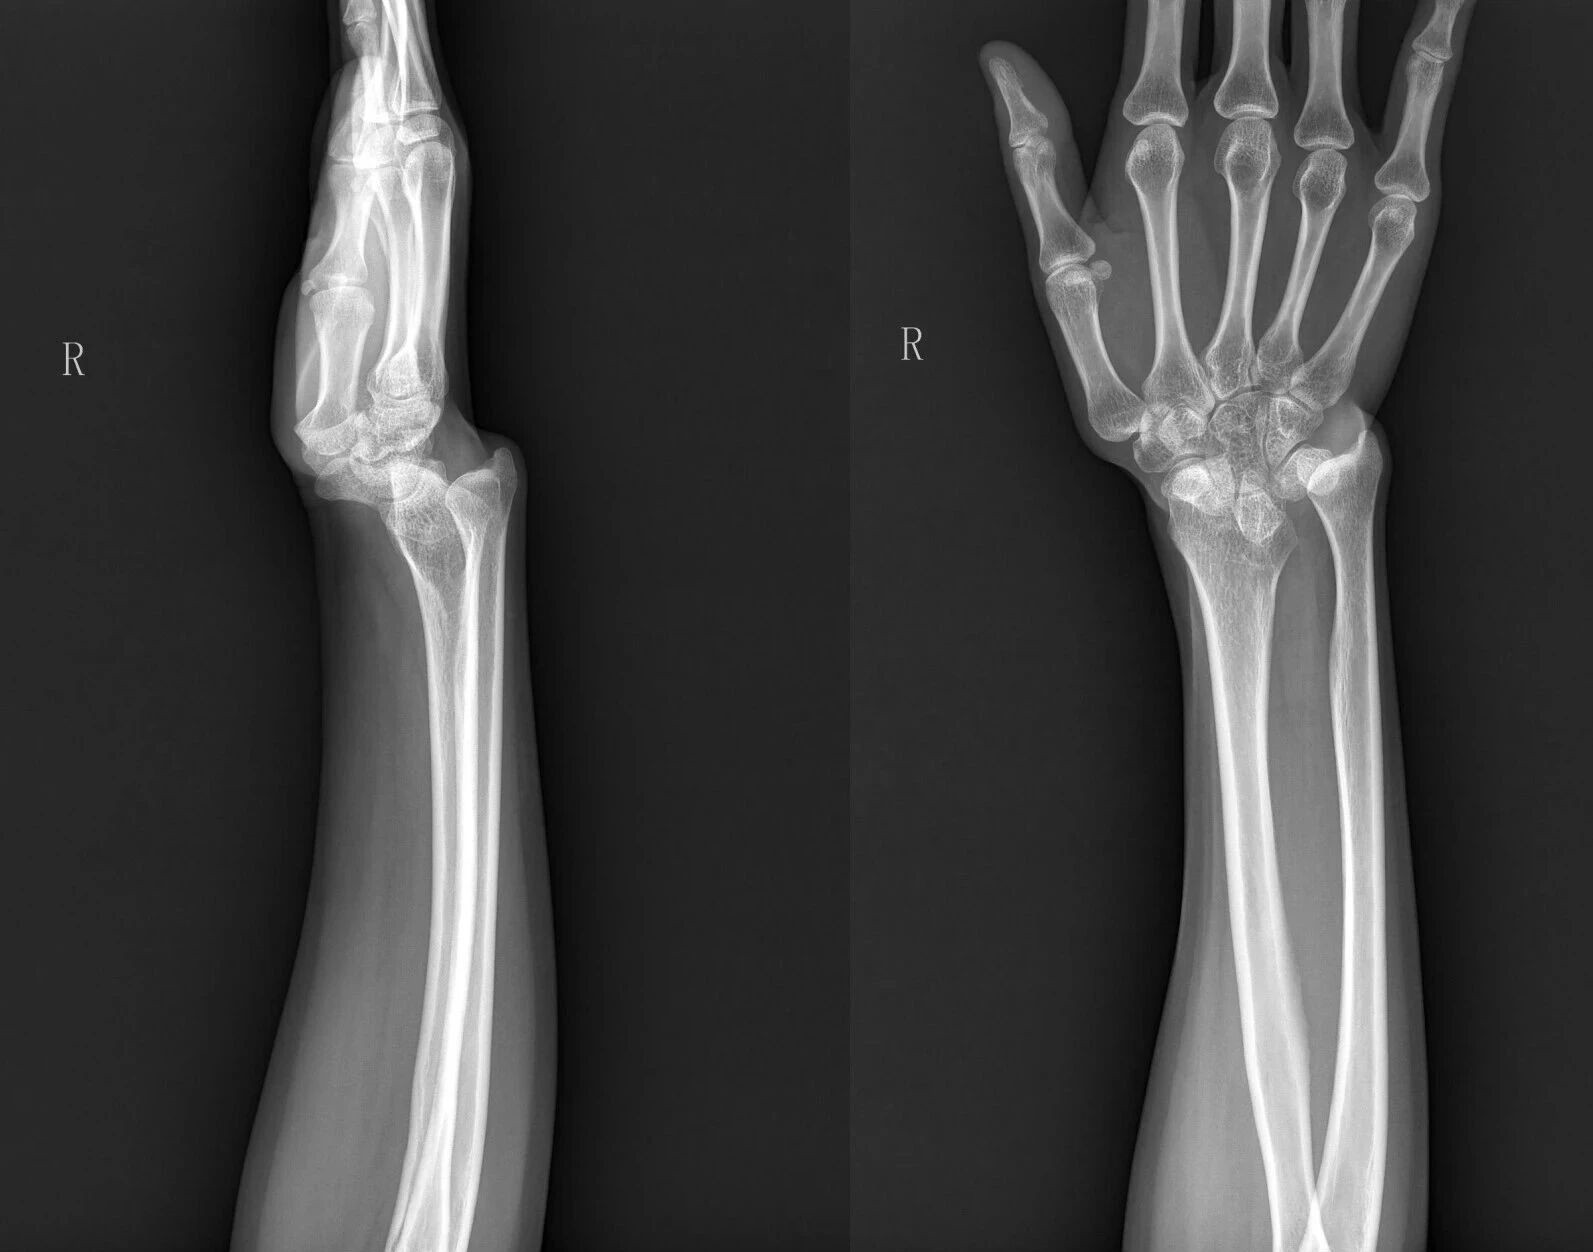

患者的术前X光影像。

接诊张女士的是顺德和平外科医院首席专家、被誉为“顺德医生楷模”的张敬良博士。经详细检查发现,由于当年张女士的桡骨远端骨折未得到规范治疗,出现桡骨短缩畸形,进而引发连锁病变。张女士最终确诊为尺骨撞击综合征、三角纤维软骨复合体损伤、下尺桡关节脱位等多项复杂合并症。

“她的手腕就像一个被‘震歪’的地基,桡骨短了,尺骨相对就长了,多出来的尺骨像锤子一样,日积月累撞击、磨损腕骨和软骨,直到把里面的‘零件’都撞坏,疼痛才会爆发。”对张女士病情的发展过程,张敬良博士形象地打了个打了比喻。